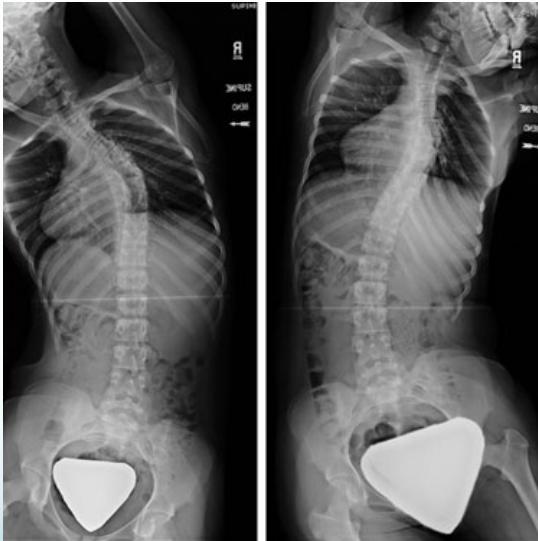

- Lat bending: For deformity assessment

- Deformity series: (e.g., scoliosis series)